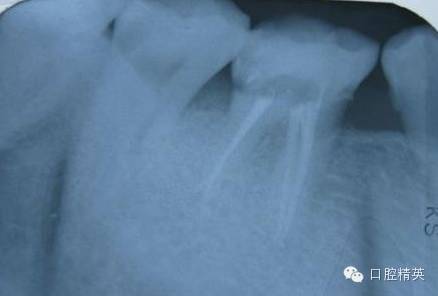

根本无法放入X光片,患者还是恶心的要命。勉强照了一张试尖的,结果没照到根尖

根充完毕,再次照,不过角度不对,重叠了。

本想再照一张,但看看痛苦的患者。。。。。

没忍心。